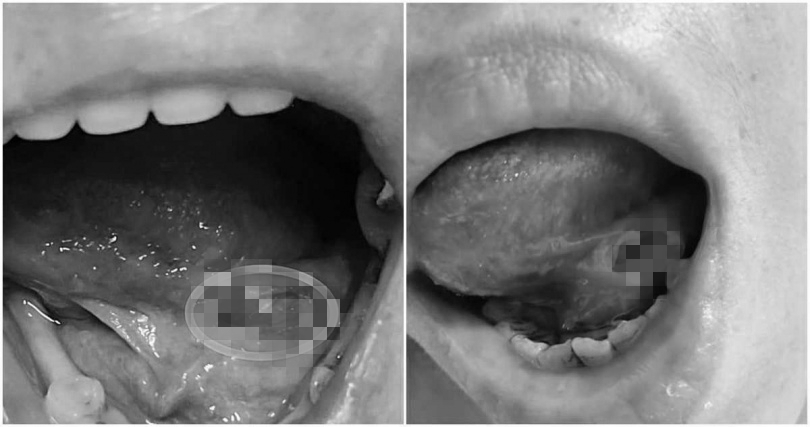

▼原PO嘴巴破洞傷口超深。(圖/翻攝自爆料公社臉書)

原PO說,「下午回去找他,才給我藥膏,我憤怒指責他,早上如果給我藥膏,我就不用再跑這趟了,醫生居然回我,破皮而已。」聽完後他超傻眼,因為傷口明明深到棉花棒頭都可以插到底了,「是破皮而已嗎?懷疑人生。」